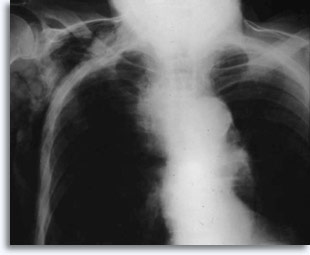

Met transthoracale percutane longaspiratie als referentiepunt, worden bloedingen verwacht als de naald door het borstvlies gaat en het longcelweefsel binnendringt. Dit is gewoonlijk zichtbaar als een versterking van de target in postpunctie borstkasfilmpjes.

Dit wordt soms in verband gebracht met zelf elimiteerde hemoptyse als een klinische reactie van de intraparenchymale lekkage. Pneumothoraxis een bijkomstig verschijnsel van tranthoracale aspiratiebiopsie omdat de naald het borstvlies beschadigt, terwijl deze zijn weg zoekt naar het parenchymatische doel, hetgeen kan resulteren in enige longcollaps. Dit is symptomatisch voor pneumothorax, hetgeen wordt beschouwd als een complicatie. In het algemeen moet er een buis in de borst worden ingebracht zodat de long weer met lucht kan worden gevuld.

Enkele factoren die het voorkomen van symptomatische pneumothorax beïnvloeden, zijn de leeftijd van de patiënt, de afmeting, plaats en diepte van de laesies, het aantal puncties, aanwezigheid van emfyseem, intensiteit van nauwkeurig onderzoek met postprocedurele films en de ervaring van de aspirator.